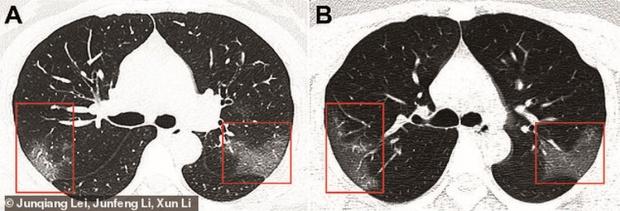

După un prim set de analize de sânge, medicii au confirmat că pacienta avea o nouă tulpină de coronavirus. Radiografiile au cât de afectați erau plămânii de infecție (imaginea A).

Trei zile mai târziu, i s-a făcut o nouă radiografie (imaginea B). Diferențele erau uriașe. Zonele afectate de virus se măriseră, ceea ce însemna că tratamentul nu funcționa.

Radiografia arată efectele COVID-19 în organismul unei tinere de 33 de ani

Imaginile au fost publicate în revista de specialitate Radiology, de un grup de cercetători de la The First Hospital of Lanzhou University, China.